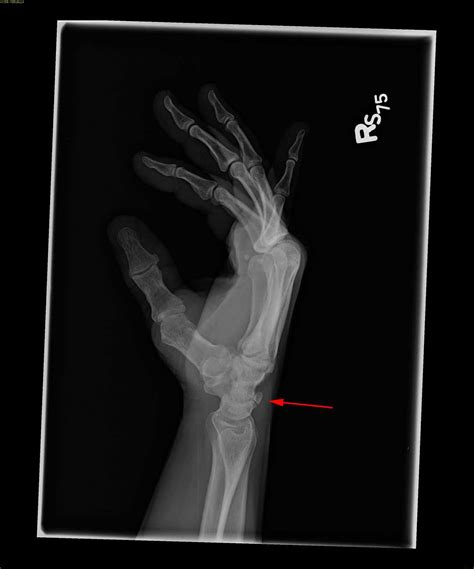

Diagnosing a fractured triquetral bone involves a combination of physical examination and imaging tests. The diagnostic process typically includes:

• Physical examination: A healthcare provider will assess the wrist for swelling, tenderness, and range of motion.

• X-rays: Standard X-rays can often reveal a fracture in the triquetral bone. However, due to the small size of the bone, additional views or specialized imaging may be required.

• CT scan: A computed tomography (CT) scan provides detailed images of the bone and can help identify fractures that are not visible on standard X-rays.

• MRI: Magnetic resonance imaging (MRI) can be used to assess soft tissue injuries and provide a more comprehensive view of the wrist joint.

In some cases, a combination of these imaging tests may be necessary to confirm the diagnosis and determine the extent of the injury.